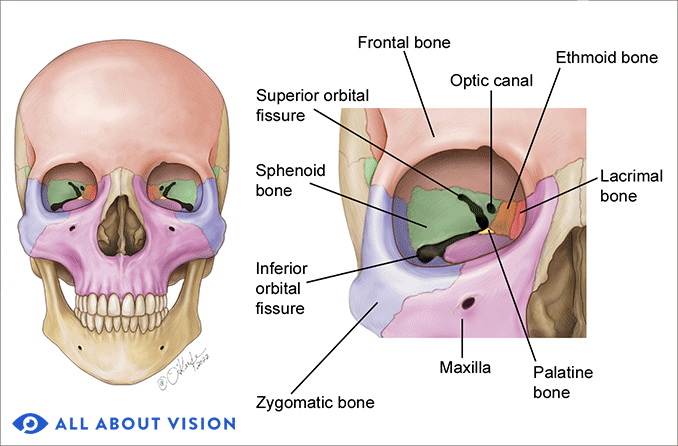

Sphenoid bone

Optic canal

- CN II

- Ophthalmic a.

-

Sup. orbital fissure

- Ophthalmic n.(CN V1)/ v.

- CN III, IV, VI

相鄰骨

F, O, T, E, Pr, V, Z, Pl, Mx

眼眶